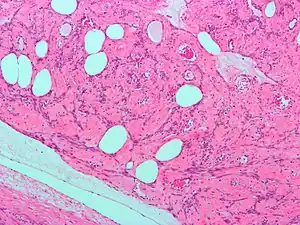

Uterine lipoleiomyoma, a type of leiomyoma. H&E stain.

A rare form of these tumors is uterine lipoleiomyoma—benign tumors consisting of a mixture of adipocytes and smooth muscle cells. Uterine lipoleiomyomata have been observed together with ovarian and other pathologies and some of them may develop into liposarcoma.[1][2] These tumors are monoclonal, and non-random chromosomal abnormalities have been seen in 40% of the tumors.